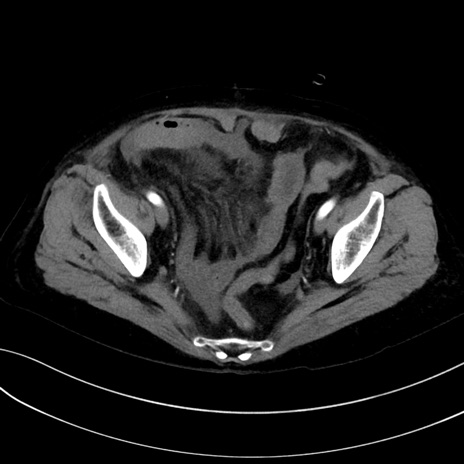

(冠状断像)1日半後